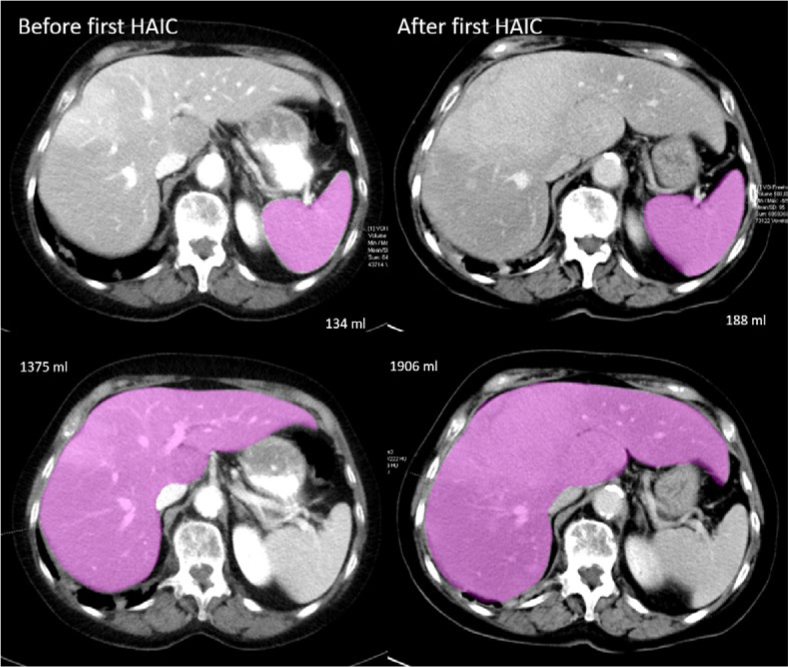

Background: Uveal melanoma (UM) patients with liver metastases often undergo hepatic artery infusion therapy (HAIC). Due to diffuse metastatic spread in the liver, patients often develop hepatomegaly and secondary, portal hypertension which may lead to splenomegaly. This study aimed to compare spleen volumetry and the change of spleen volume (SV) for the evaluation of HAIC treatment response.

Patients and methods: In this study, 179 UM patients (mean age 64.8 ± 11.0y, 53% female) with liver metastases undergoing HAIC were included. Treatment response was analyzed by RECIST 1.1 and SV on CT imaging before and after first HAIC. The correlation of change in spleen and liver volume was analyzed with Spearman test. Overall survival (OS) was calculated as the time from the first HAIC to patient death using Kaplan-Meier test and multivariate analysis was performed for RECIST 1.1 and SV.